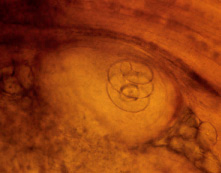

A, B: Encysted larvae of Trichinella in pressed muscle tissue sample.  The coiled larvae can be seen inside the cysts.